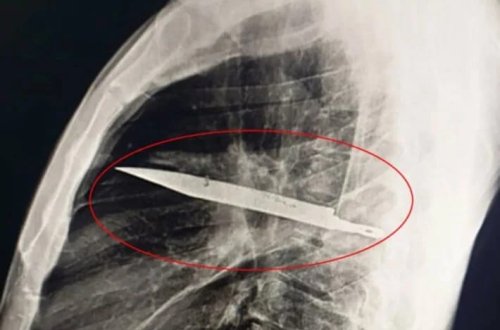

Ağrıdan şikayət edərək xəstəxanaya getdi, sinəsindən bıçaq tapıldı

ildir

səkkiz

sinəsində

bıçaqla

məlum

yaşadığı

kişinin

gedən

verir

xəbər

tanzaniyada

ağrı

xəstəxanaya

şikayəti

7news